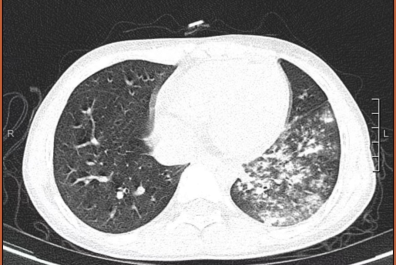

一拍片发现肺部出现了炎症

还融合成了片状

支原体呼吸道感染临床表现呈多样性,可从无无症状到鼻咽炎、鼻窦炎、中耳炎、扁桃体炎、气管支气管炎和肺炎等,肺炎支原体肺炎的主要临床表现是发热、咳嗽、肺部体征与临床症状及影像所见不一致。

只有少部分感染者会发展为肺炎。肺炎支原体肺炎(MPP)以发热、咳嗽为主要临床表现,可伴有头痛、流涕、咽痛、耳痛等。发热以中高热为主,持续高热者预示病情重。咳嗽较为剧烈,可类似百日咳样咳嗽,婴幼儿以喘息为主要表现多见。肺部早期体征可不明显,随着病情进展可出现呼吸音降低和干、湿性啰音。